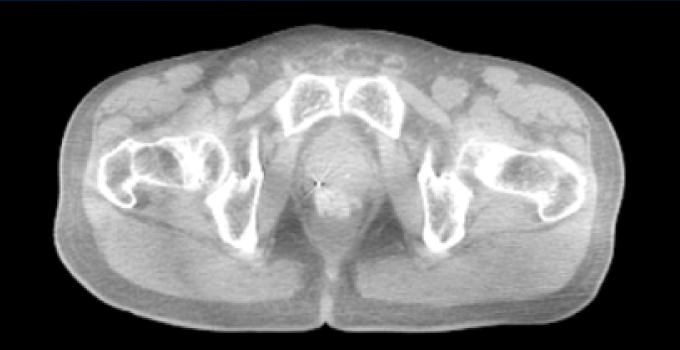

SpaceOAR Vue Hydrogel in different image modalities

Computed Tomography images.

Computed Tomography images*

*Jeff Michalski, M.D. [2020]. Permission granted by Washington University Image.